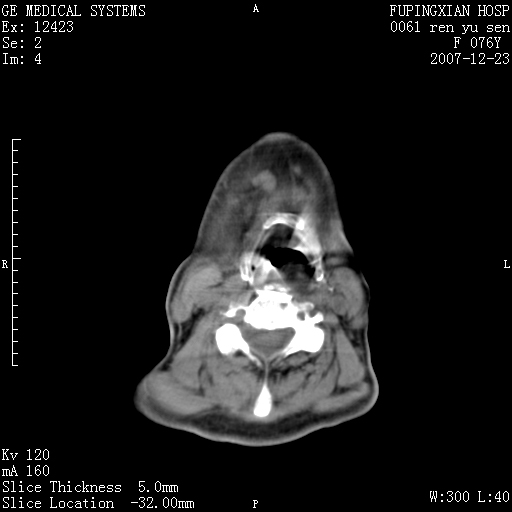

男性 76岁 下颌右侧磨牙区肿物数月, 约2.0*1.5cm大小波及颊舌侧,伴颌下淋巴结肿大。余(-)

右颈部颌下腺前可见一类圆形软组织密度影,密度不均,内见小片坏死区.颌下颈前可见两枚肿大淋巴结影.考虑淋巴结感染可能性大,建议增强扫描..

右侧第四磨牙缺失,局部牙槽骨质破坏,边界欠清晰,同侧颌下及竟不见多发肿大淋巴结显示。考虑肿瘤病变可能性大,感染待排